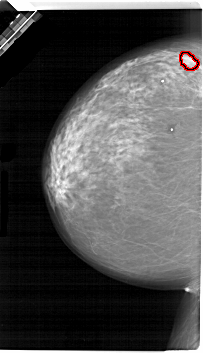

A_1657_1.LEFT_MLO

LEFT_MLO LINES 6721 PIXELS_PER_LINE 4246 BITS_PER_PIXEL 12 RESOLUTION 43.5 OVERLAY

FILE: A_1657_1.LEFT_MLO.OVERLAY

TOTAL_ABNORMALITIES 1

ABNORMALITY 1

LESION_TYPE MASS SHAPE LOBULATED MARGINS OBSCURED

ASSESSMENT 4

SUBTLETY 3

PATHOLOGY MALIGNANT

TOTAL_OUTLINES 1

BOUNDARY